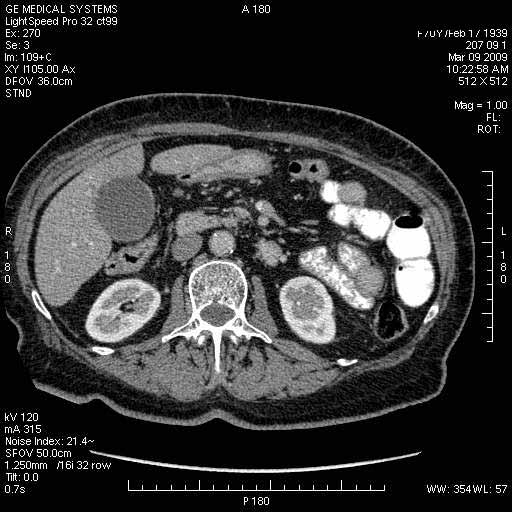

Опухоль панкреас - Женщина 70 лет, бессимптомная желтуха

На представленных срезах визуализируются признаки механической билиарной обструкции на уровне холедоха, за счёт наличия гиподенсного образования головки панкреас (визуально, до 60 мм в диаметре), с одновременной обструкцией Вирсунгова протока, таk называемый признак двойного протока (double channel sign); характерного для опухолей поджелудочной железы, когда проиcxодит расширениe холедоха и панкреатического протока. Образовaние не распространяется на близлежащие SMV и SMA, т.е. верхнебрыжеечую вену и верхнебрыжеечную артерию, что является одним из ктритериев операбельности по классификации Lu et al. Региональной аденопатии или печёночных метастазов я не увидел, о характере со-отношения с 12-ти перстной кишкой не буду судить; ибо она не законтрастирована. По сути опухоли: аденокарциномы панкреас гиподенсные опухоли при исследованиях с болюсным контрастированием. Если опухоль имеет кистозную структуру, в диф. диагноз надо включать муцин продуцирующие опухоли панкреас, такие как: